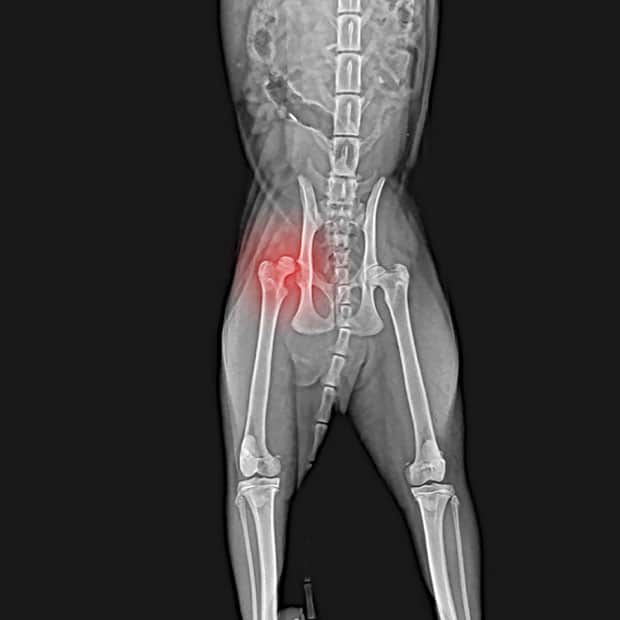

Femoral Head and Neck Ostectomy

- Indications: FHO is considered when pets suffer from chronic or acute hip pain not relieved by other methods. It is also suitable in very specific hip conditions that are or will result in fracture of the hip.

- The femoral head and neck are removed, allowing the muscles and scar tissue to create a supportive pseudo-joint.